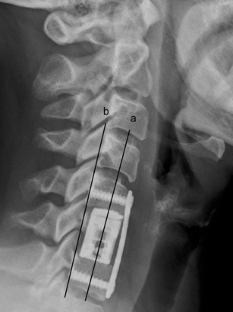

Fig. 4